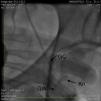

A 51-year-old white man with a history of hypertension and tobacco abuse and a strong family history of premature coronary artery disease was initially admitted to our hospital with worsening chest pain and underwent pharmacological stress testing, which showed distal anterior and apical wall ischemia with preserved left ventricular systolic function. He was referred for coronary angiography, initially performed using a 6F system and right femoral artery access. A 95% lesion of the left anterior descending artery with thrombus was stented without complications. He continued to have chest pain and a second intervention via the left groin was performed four days later on a 80–90% stenosis of the mid right coronary artery (RCA) and 80% stenosis of the mid posterolateral ventricular branch (PLV). During the procedure a 0.035inch wire and 6F sheath were advanced without difficulty. The RCA was engaged with a 6F Amplatz Left (AL) 0.75 guiding catheter (GC) (Cordis, Miami Lakes, FL) for better back-up and a 0.014inch Balance Middle Weight (BMW) wire was advanced to the distal PLV without difficulty. Both lesions were predilated with a 3.0mm×12mm compliant balloon and 3mm×15mm Vision and 4.5mm×18mm Ultra stents were placed in the PLV and mid RCA, respectively, without difficulty and with an optimal result (Figures 1 and 2). During the last cineangiogram, with the BMW wire inside the guide but outside the coronary artery, the AL GC became disengaged. We attempted to reengage the RCA but were unsuccessful, and could not transmit torque through the GC. Fluoroscopy revealed kinking of the distal GC in the external iliac artery. During attempts to straighten the GC by counterclockwise rotation, the guiding catheter fractured into two pieces (Figure 3). The proximal broken piece came out with the sheath and manual pressure was applied. The BMW wire was still firmly attached to the guide. An 8F arterial sheath was then introduced partially up the broken GC over the BMW wire, the introducer sheath was removed, and attempts were made to advance a loop snare next to the kinked GC, with no success, and to advance a 0.035inch J-tip wire next to the GC, also without success. At this time, the other option was to obtain access by the right femoral or brachial/radial artery to try to snare the proximal or distal end of the GC, but there were concerns because of the significant kink potentially traumatizing the exit vessel, especially with a brachial/radial approach. While we were considering advancing a 15-mm Amplatz gooseneck snare (ev3 Inc., Plymouth, MN) over the wire to snare out the distal fragment, it was decided to use the unusually firmly stuck BMW wire as an advantage and to pull back the wire while simultaneously advancing the 8F sheath over the GC. The BMW wire was pulled back rotating a hemostat in a counterclockwise direction and the sheath was advanced while clockwise rotation was applied, which enabled the GC to be straightened; we were able to withdraw the GC inside the sheath (Figure 4), then the sheath was pulled out with the GC inside. Although the distal portion of the fractured GC was out, we were still unable to remove the BMW wire (Figure 5); we therefore cut the guiding catheter proximal to the kink, removed the BMW wire and inserted a J-wire, removed the remaining GC and then reinserted the 8F sheath. The femoral angiogram showed tortuous iliac arteries with a small leak on the medial side of the sheath with no dissection or perforation (Figure 6). A FemoStop was applied at low pressure to stop the leak around the sheath, and the sheath was then removed once active clotting time was <150s. Hemostasis was achieved using manual pressure, and then a FemoStop was applied at low pressure for two more hours, followed by bed rest for a total of eight hours. The patient remained stable and asymptomatic throughout the procedure and overnight, and ambulated without difficulty the next day. The following day, before he was discharged, he went to the bathroom and had to strain, and subsequently developed acute left groin swelling and pain. Examination revealed a palpable hematoma suggestive of pseudoaneurysm. An ultrasound exam confirmed the existence of a 4.2cm×2.9cm pseudoaneurysm which was treated with ultrasound-guided compression. He was subsequently ambulating with no difficulty and was discharged home, and no new problems occurred during follow-up.

Unfortunately, in our patient a slight counterclockwise rotation fractured the GC. Part of the reason for this could be the three knots in the GC visible after it was withdrawn (Figure 5), suggesting multiple kink points in a highly tortuous iliac artery making multiple three-dimensional turns (Figure 6). This was probably also the reason for the BMW wire entrapment.